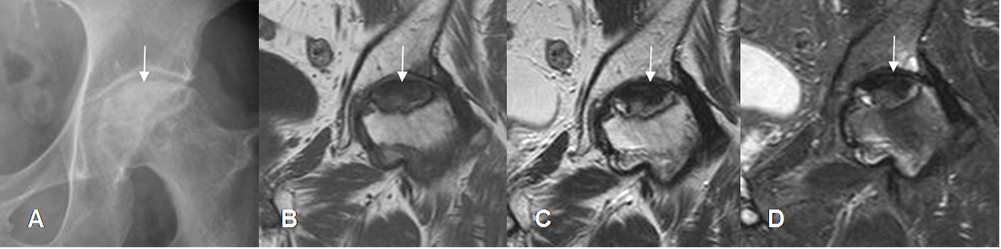

Fig 24 B. Osteonecrosis de cadera.

A: Rx AP. Aumento en la densidad y pérdida de la morfología de la cabeza femoral.

B: RM coronal en T1, C: RM coronal en T2 y D: RM coronal en STIR. Lesión hipointensa

en todas las secuencias sobre la cabeza femoral, por osteonecrosis de evolución crónica.